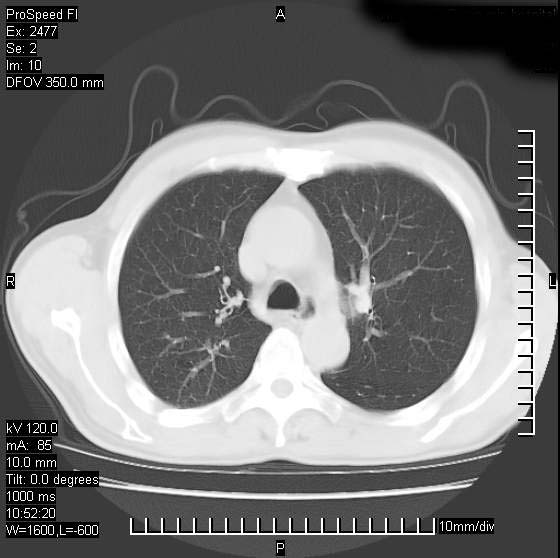

以下是引用天南地北在2007-10-9 14:29:00的发言:[br]1:右上肺结核[br]2:右肺下叶肿块:不支持肺癌,首先考虑炎性病变-肺脓疡可能性大[br]理由:1:临床病史支持,肺脓肿症状不明显应该是不规则服药造成。[br] 2:肿块边缘模糊,周围可见炎性渗出,长毛刺,内见支气管征,不过有点不规则。[br] 我感觉下肺癌这个诊断有点偏左,建议积极抗炎治疗后复查

以下是引用卜一在2007-10-9 15:55:00的发言:[br][br] [br] 1:右上肺结核[br]2:右肺下叶肿块:不支持肺癌,首先考虑炎性病变-肺脓疡可能性大[br]理由:1:临床病史支持,肺脓肿症状不明显应该是不规则服药造成。[br] 2:肿块边缘模糊,周围可见炎性渗出,长毛刺,内见空气支气管征,不过有点不规则。[br] 我感觉下肺癌这个诊断有点偏左,建议积极抗炎治疗后复查![br]支持! [br] [br] [br]

以下是引用wxy7406在2007-10-9 21:02:00的发言:[br]结合临床病史首先考虑感染性病变,但周围型肺癌不能除外,1.患者年龄偏大2.临床有咯血3.(也觉得是最重要的一点)病灶内有偏心性空洞。

以下是引用王仕学在2007-10-9 13:48:00的发言:[br]右下肺周围性肺癌可能性大,最好活检吧

以下是引用hhcckk在2007-10-9 15:18:00的发言:[br]右上肺病灶考虑结核,病灶多种形态并存(纤维化、增殖性病灶并存)[br]右下肺病灶比较难说,个人意见更趋向于“天南地北”的诊断----肺脓肿[br]1、病人有明显的寒战,高热,肿瘤病人很少出现[br]2、病灶周围的肺纹理走向柔和,没有肿瘤病灶常见的集束征[br]3、病灶边缘的毛刺较长,恶性肿瘤多为短毛刺[br]痰中血丝和病人的年龄是两个不利于良性肿块的因素,建议早点活检

以下是引用ydx_74在2007-10-9 15:53:00的发言:[br]右上肺结核,右下中心性肺癌可能大,肺门淋巴结肿大。